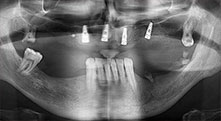

Pourriez-vous décrire brièvement par exemple comment vous procédez pour mobiliser les blocs osseux en vue d’une greffe ?

Pr Bratu : Nous préférons prélever l'os sur la crête oblique externe de la mandibule postérieure, et non dans la région interforaminale. Après l'incision des tissus mous, nous utilisons les nouvelles scies pour définir la quantité d'os à prélever. De la même manière, nous les utilisons également pour la totalité de la préparation dans presque 80 % des cas. Nous avons également parfois recours à d'autres instruments piézoélectriques et, pour terminer, à un burin pour mobiliser le bloc. Nous trouvons cette technique chirurgicale très efficace.

Pr Bratu : J'estime que la chirurgie piézoélectrique a fait faire un grand bon en avant à la chirurgie orale. Grâce à cette technique, la préparation osseuse est plus sûre et plus facile. Par exemple, les extractions entraînent une perte osseuse minime. C'est très important d'un point de vue esthétique, surtout si la pose d'implants est prévue immédiatement.